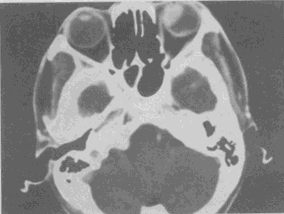

男,37岁,半年来视力下降明显,近1个月失明,CT如图,最可能的诊断是

A.色素膜黑色素瘤伴视网膜脱离

B.色素膜血管瘤伴视网膜脱离

C.色素膜转移瘤伴视网膜脱离

D.色素膜神经瘤伴视网膜脱离

E.黑色素细胞瘤伴视网膜脱离

[单选题]男,37岁,半年来视力下降明显,近1个月失明,CT如图,最可能的诊断是A.色素膜黑色素瘤伴视网膜脱离B.色素膜血管瘤伴视网膜脱离C.色素膜转移瘤伴视网

[单选题]男,37岁,半年来视力下降明显,近1个月失明,CT如图,最可能的诊断是A.色素膜黑色素瘤伴视网膜脱离B.色素膜血管瘤伴视网膜脱离C.色素膜转移瘤伴视网膜脱离D.色素膜神经瘤伴视网膜脱离E.黑色素细胞瘤伴视网膜脱离